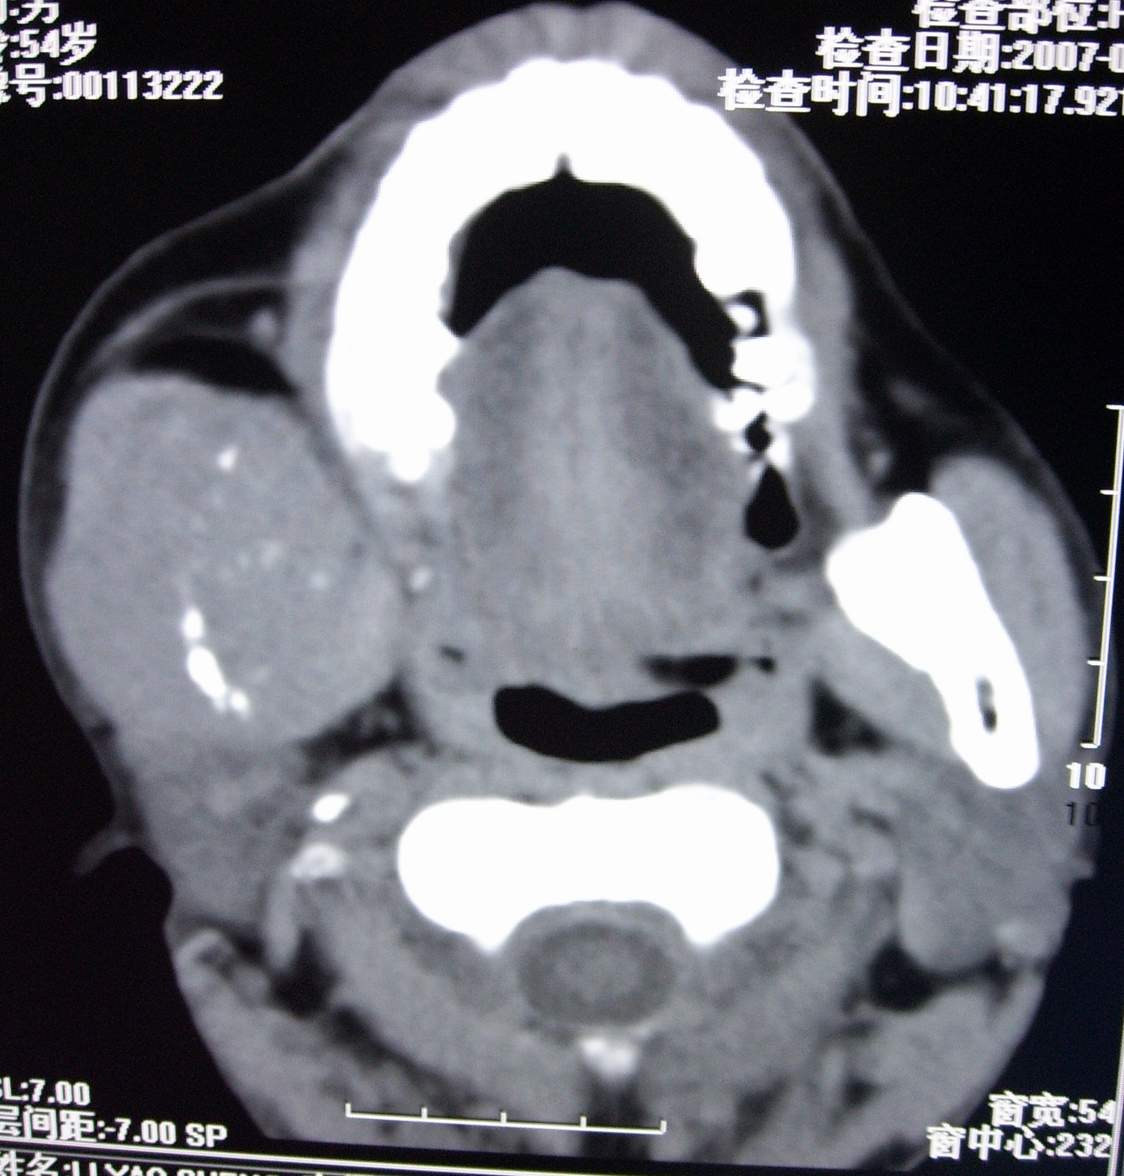

男,54岁,右下颌肿痛1月余。

右下颌骨溶骨性破坏,并见软组织形成。应考虑恶性肿瘤或转移瘤。

右侧下颌骨水平部及升支呈溶骨性破坏,无明显膨胀,周围见软组织肿块。

考虑:右侧下颌骨恶性肿瘤或转移瘤。

右下颌骨恶性骨肿瘤伴右颈部淋巴结转移。

右下颌骨溶骨性破坏,代之以团块状软组织影,内有斑片状瘤骨,边缘骨质有少量骨膜反应,考虑:右下颌骨骨肉瘤。期待病理。